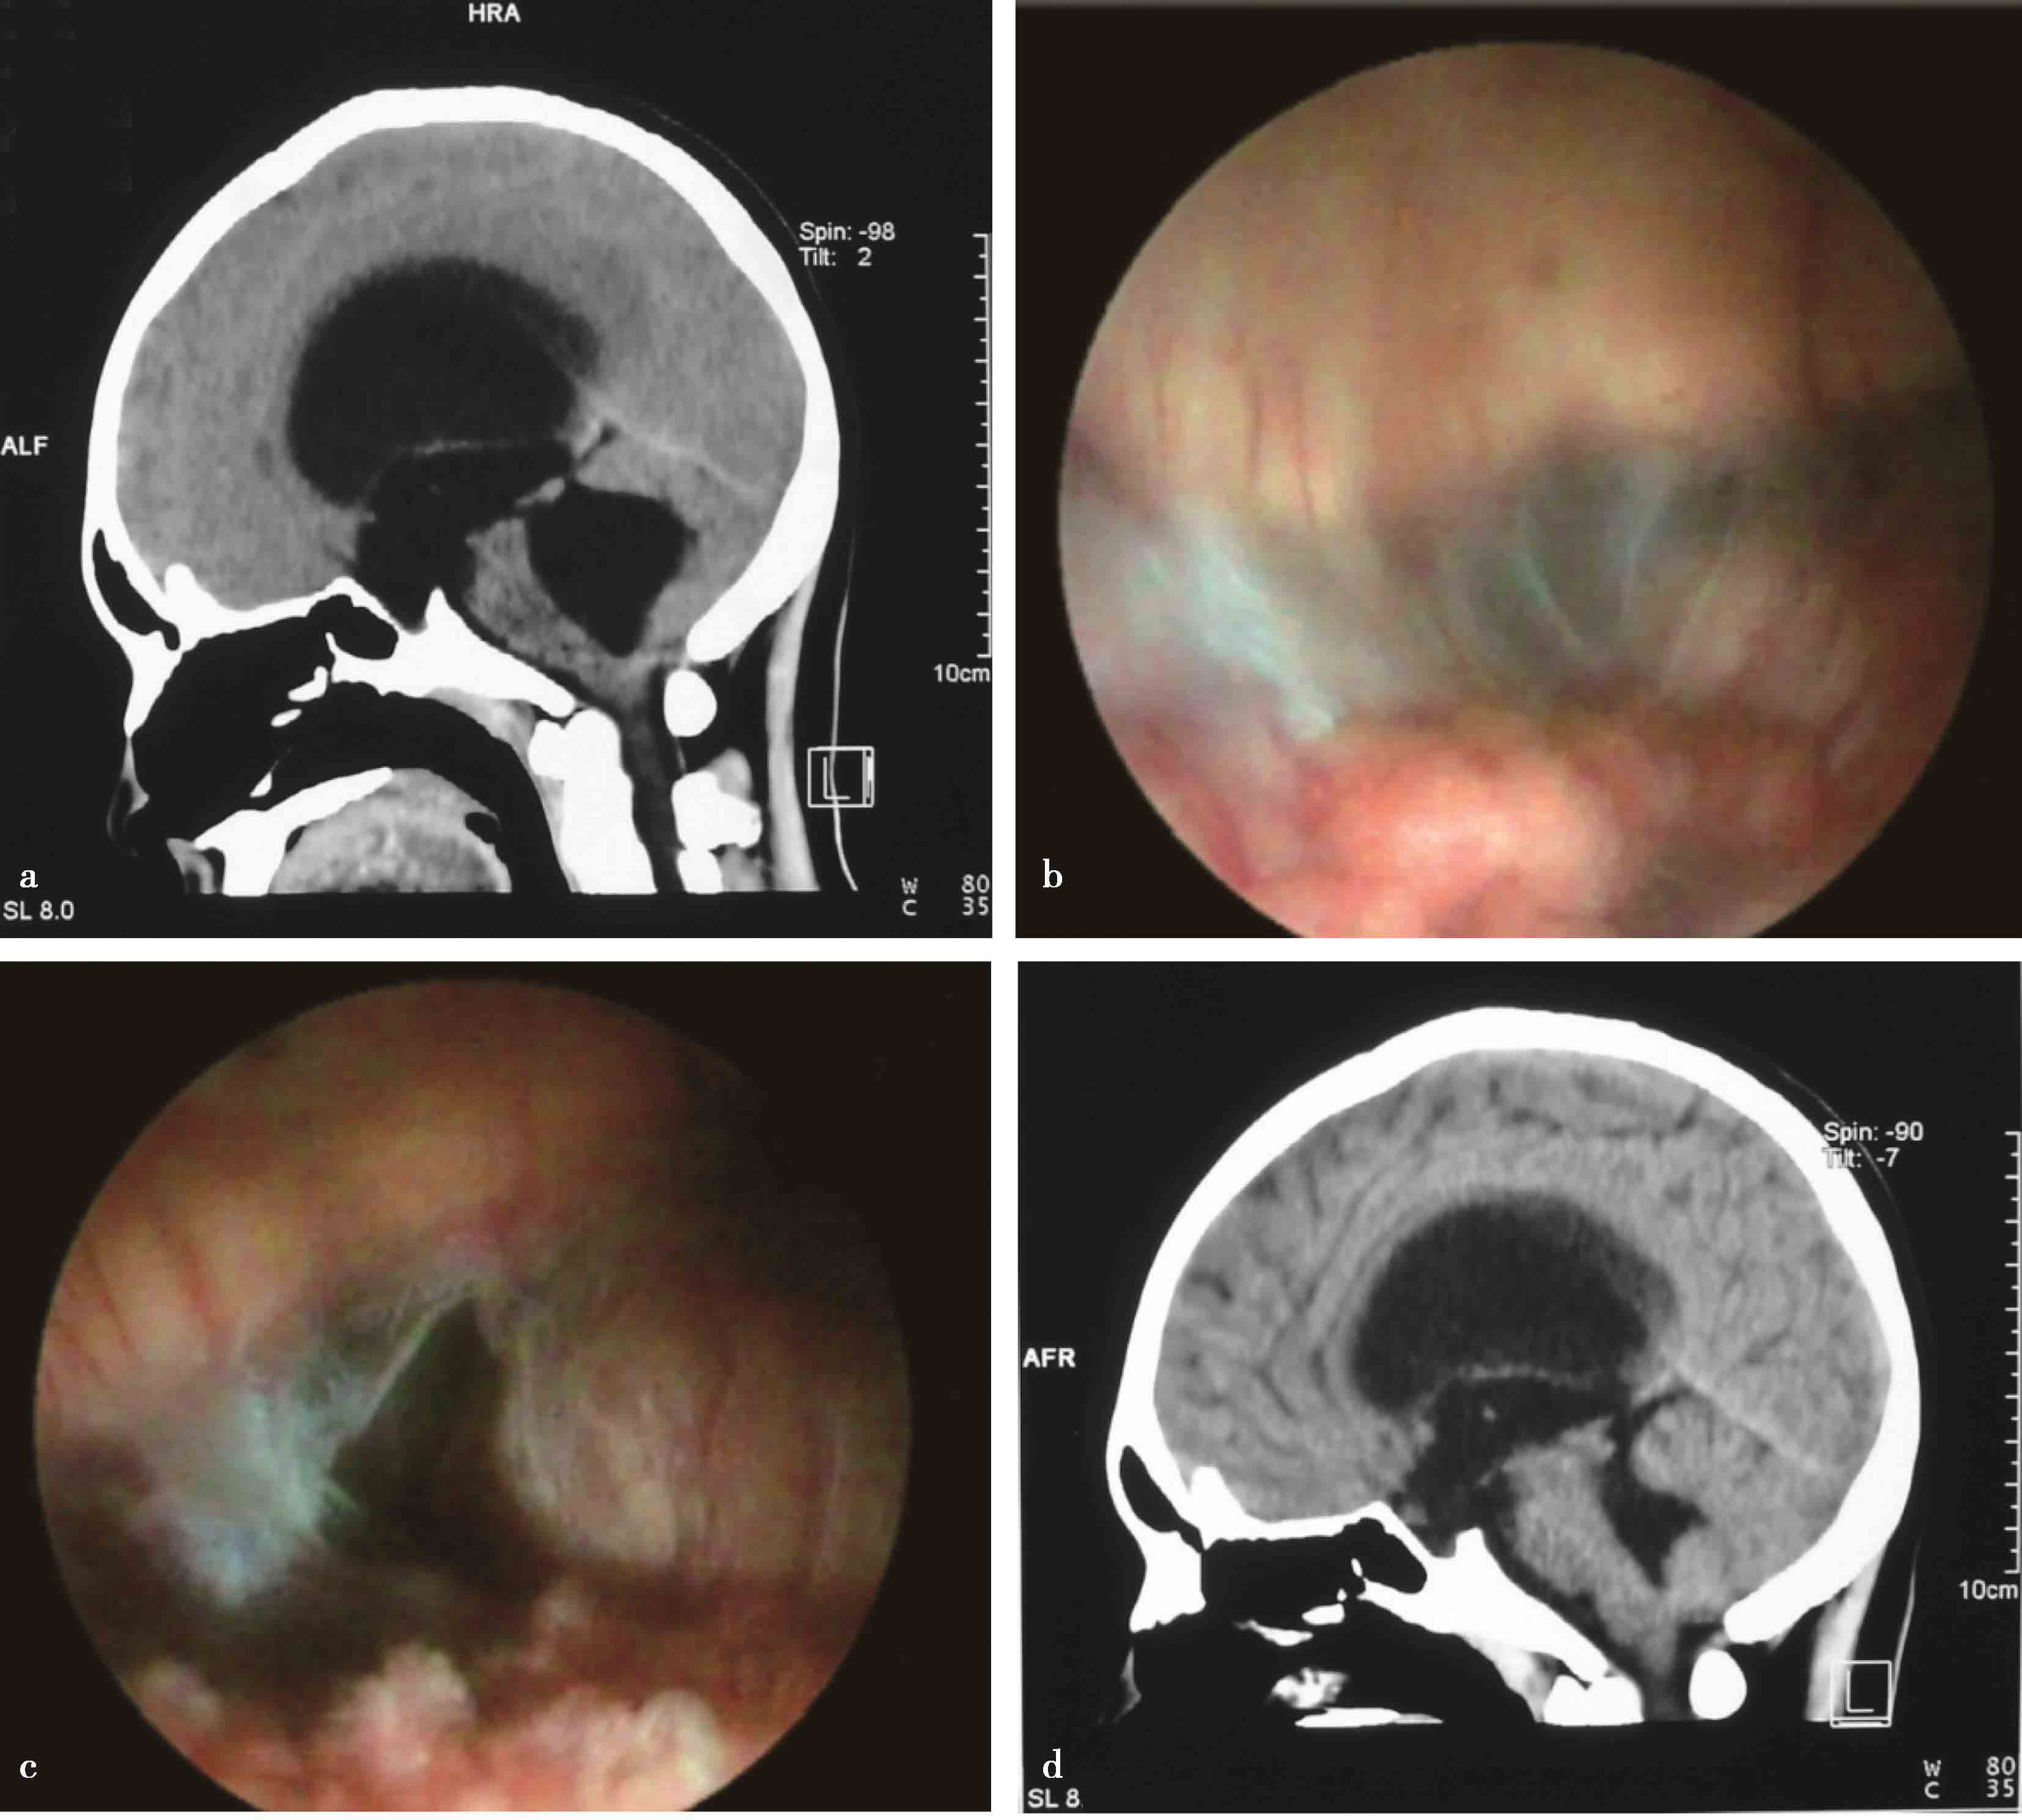

4.导水管节段性狭窄或膜性闭塞所致梗阻性脑积水以及孤立第四脑室,采用导水管成形术,必要时支架植入术进行治疗(图3-1-2-4~图3-1-2-6)。

图3-1-2-6 孤立第四脑室,内镜下见

5.第四脑室流出道(包括正中孔和双侧侧孔)膜性闭塞,也可采用第四脑室正中孔成形术进行治疗(图3-1-2-7)。

图3-1-2-7 第四脑室流出道梗阻

a.矢状位片示第四脑室明显扩张;b.内镜下探查见第四脑室正中孔膜性闭塞;c.内镜下第四脑室正中孔成形;d.术后10个月复查第四脑室明显缩小;e.正中孔(Magendie孔)闭塞,结构紊乱富含血管;f.探查右外侧孔(Luschka孔);g.探查左外侧孔(Luschka孔)